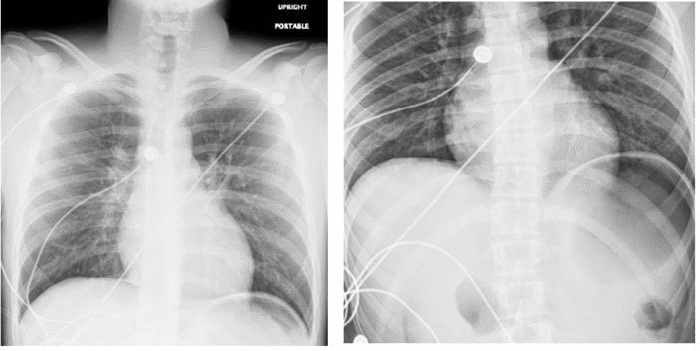

On postoperative day one, the patient was started on a clear liquid diet. The following day, the patient passed flatus approximately five times. However, on postoperative day 3, the patient developed abdominal distention, nausea, and three episodes of emesis. An abdominal radiograph series revealed dilated loops of small bowel with multiple air-fluid levels but no additional intraperitoneal free air (Figure 2). Consequently, on postoperative day four, the patient’s diet was discontinued, a nasogastric tube was placed, and successful decompression of the abdomen was achieved. The following morning, the patient tolerated advancement to a full liquid diet and passed a small bowel movement. He was discharged home on postoperative day 5 with a regular diet.

Figure 2. Radiographic Findings of Small Bowel Obstruction. Published with Permission

(Left) Supine and (right) upright abdominal radiographs demonstrating dilated loops of small bowel with multiple air-fluid levels, indicative of small bowel obstruction